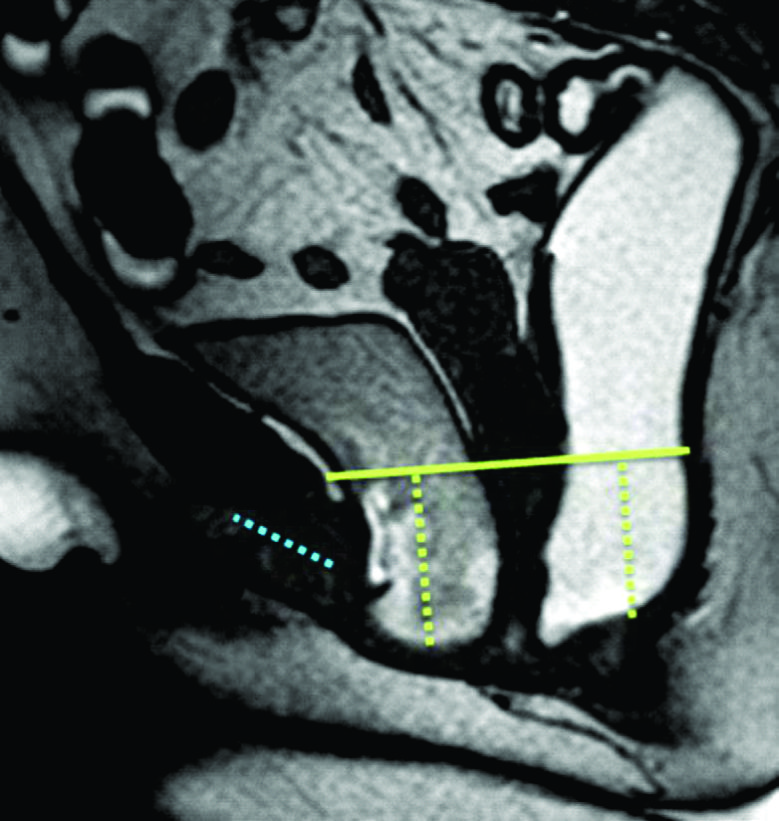

Figura 4

Línea H y línea M.Imágenes potenciadas en T2 de alta resolución en el plano sagital. Se observa el cambio en el valor que adopta la línea M y la línea H al comparar el reposo frente a la defecación. Según sus medidas en centímetros, se puede graduar en cuatro estadios diferentes.